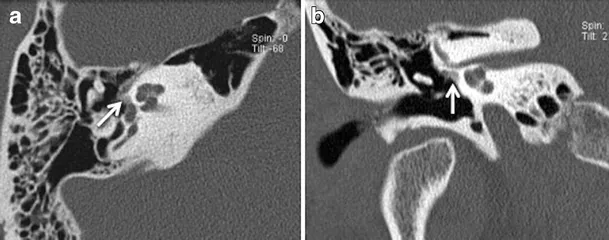

| Unilateral CHL + normal TM | Ossicular fixation | 90% | CT temporal bones |

| CT Findings | Lucent focus | Ossicular erosion | Soft tissue/erosion | Canal atresia | Normal bones |